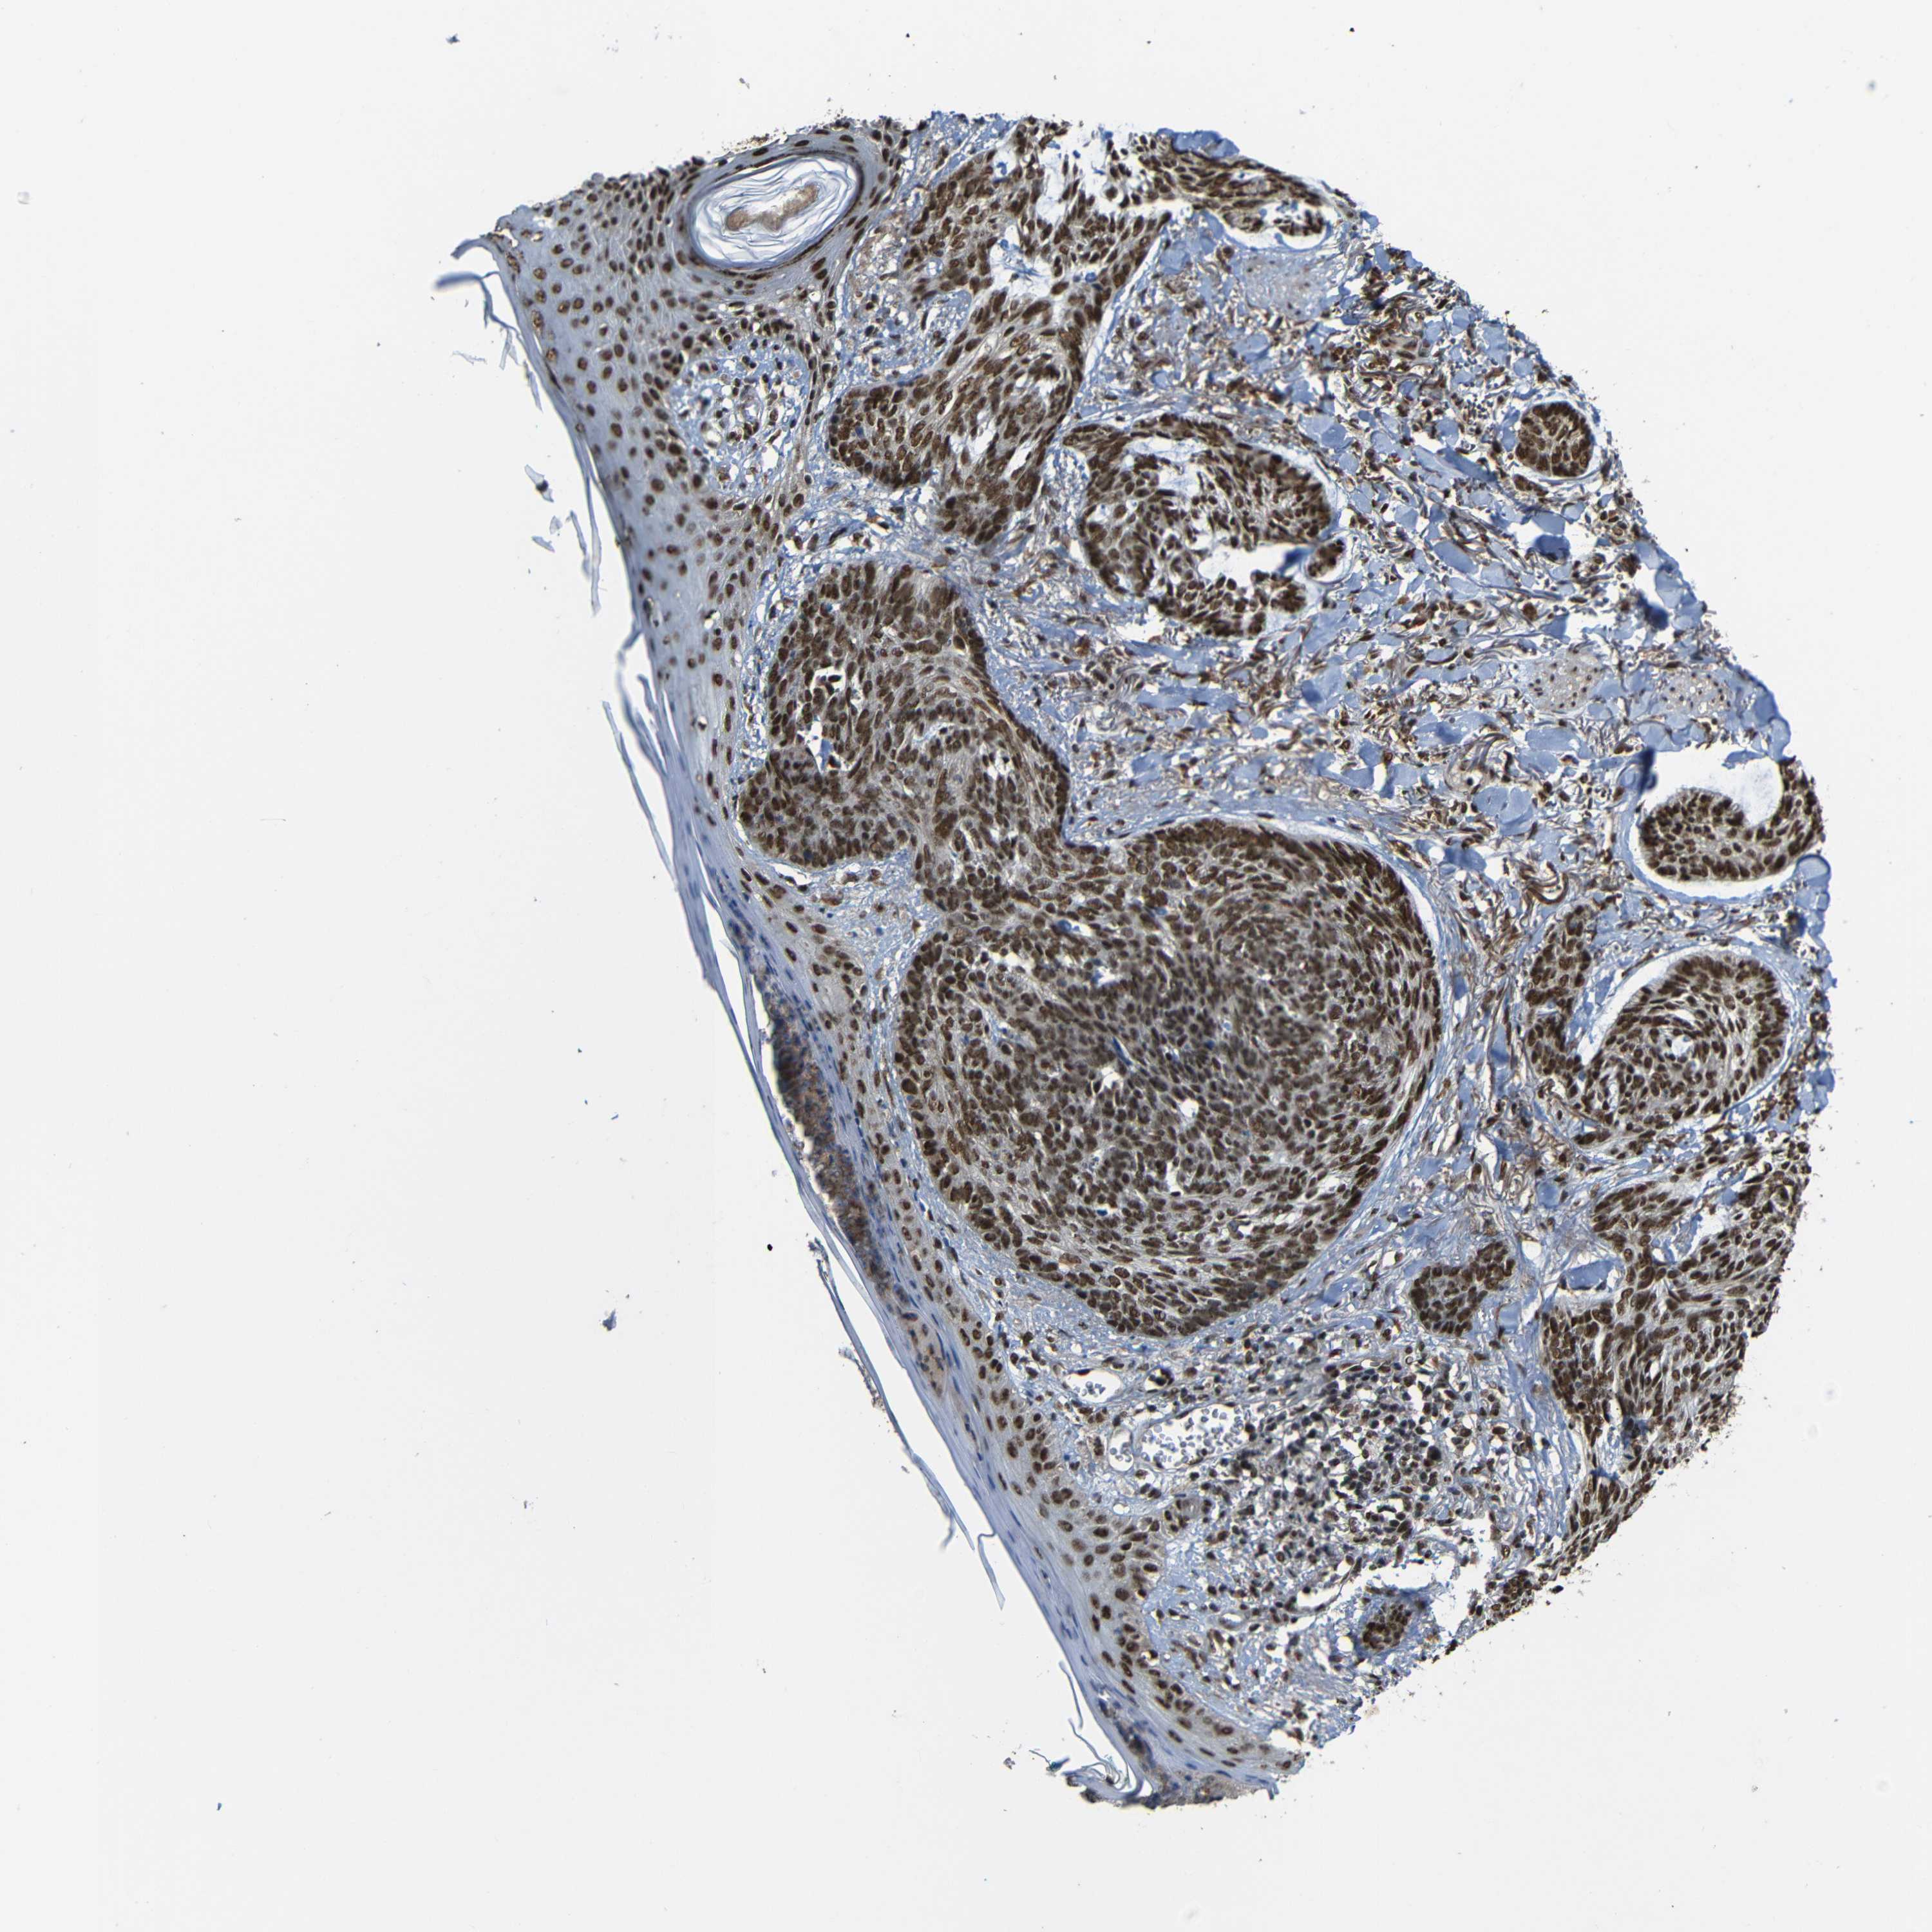

Basal cell and squamous cell cancer

SKIN CANCER - Protein expressioni

A mouse-over function shows sample information and annotation data. Click on an image to view it in a full screen mode. Samples can be filtered based on level of antibody staining by selecting one or several of the following categories: high, medium, low and not detected. The assay and annotation is described here.

Antibody stainingi

Antibody staining in the annotated cell types in the current human tissue is reported as not detected, low, medium, or high, based on conventional immunohistochemistry profiling in selected tissues. This score is based on the combination of the staining intensity and fraction of stained cells.

Each image is clickable and will lead to virtual microscopy that enables deeper exploration of all samples and also displays staining intensity scores, fraction scores and subcellular localization as well as patient and tissue information for each sample.

Antibody CAB013535

Staining

High

Intensity

Strong

Quantity

>75%

Location

Nuclear

Squamous cell carcinoma, NOS

Basal cell carcinoma